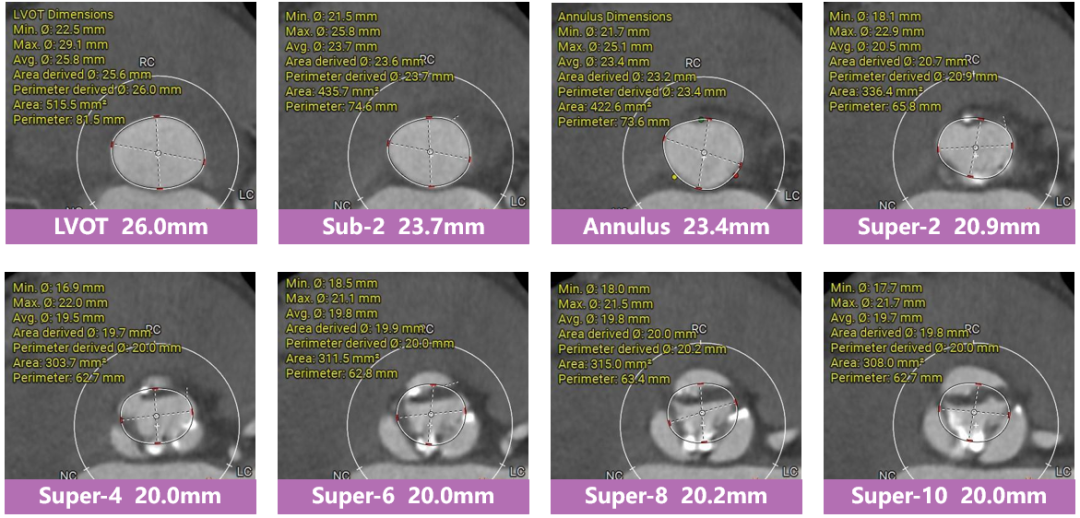

三叶瓣,窦部空间可,心室明显扩大。

多平面分析

敞口状流出道,瓣上限制较重,瓣膜释放后存在一定下滑风险。

冠脉分析

冠脉开口高度可,未见冗长瓣叶,预估冠脉遮挡风险较低。

手术策略及难点分析

• 三叶瓣,瓣叶中重度钙化,瓣膜锚定力可,瓣上限制较重,预估瓣膜释放后存在一定下滑风险;

• EF值34%,心腔增大,心功能较差,术中潜在循环崩溃及心室损伤风险;

• 预计采用22mm球囊预扩,植入TaurusElite AV26瓣膜,工作位充分评估瓣膜位置、形态、冠脉灌注及瓣周漏情况,确认无误再行释放,ECMO备台。